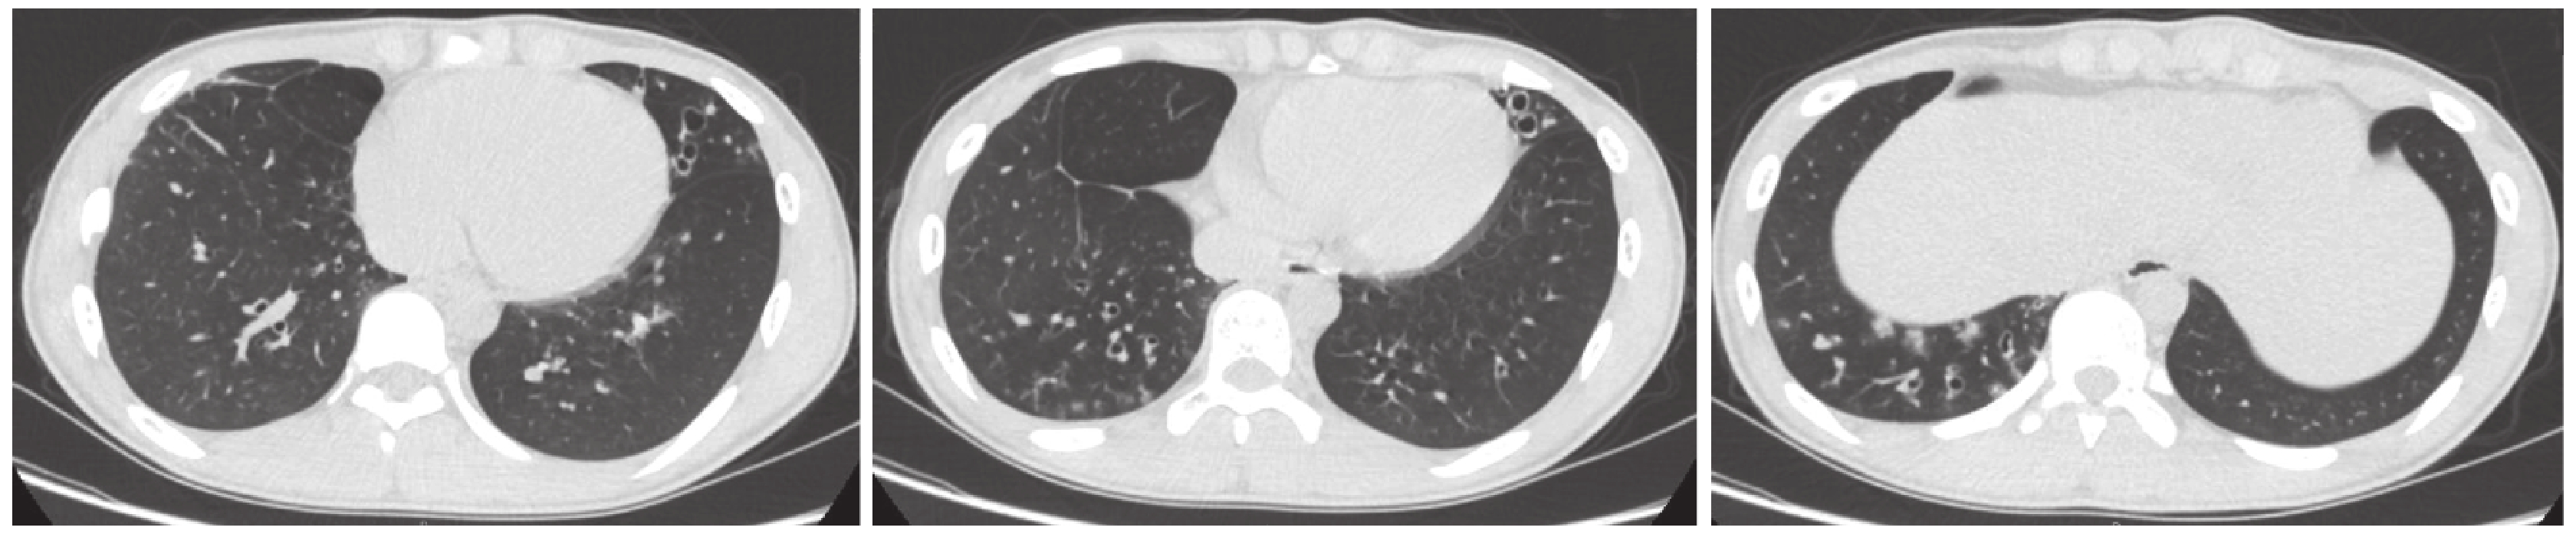

初步診斷支氣管擴張、鼻竇炎、中耳炎。入院后查血尿便常規正常,血沉 7 mm/1 h。痰涂片找抗酸桿菌陰性,痰培養陰性,血 T-SPOT-TB 陰性,類風濕因子、抗核抗體譜、抗中性粒細胞胞漿抗體陰性,HIV 抗體陰性,血清免疫球蛋白 A 2.79 g/L(正常值 0.81~2.32 g/L),肺功能顯示為阻塞性通氣功能障礙,FEV1%pred 73.0%,支氣管舒張試驗陽性,彌散功能正常。聽力測聽示雙耳傳導性耳聾,左側明顯。耳鏡檢查顯示左側化膿性中耳炎,右側中耳炎后遺癥。糖精試驗陰性,汗液鉀離子濃度 44.5 mmol/L,鈉離子濃度 44.6 mmol/L。鼻竇 CT 未見明顯異常;胸部高分辨率 CT(HRCT)顯示右肺中葉切除術后,左肺舌葉和右肺下葉支氣管擴張,部分細支氣管腔內可見軟組織密度影(圖 2)。借閱外院病理切片于我院病理科會診結果:(右肺中葉)慢性化膿性細支氣管炎,支氣管擴張,淋巴濾泡性細支氣管炎,肺泡腔內廣泛出血,肺泡上皮細支氣管化生(圖 3)。診斷為濾泡性細支氣管炎(follicular bronchiolitis,FB),予阿奇霉素 0.25 g Qod 口服,福莫特羅/布地奈德 4.5/160 μg 1 吸 Bid 吸入治療。目前仍治療隨訪中,病情穩定。

左肺舌葉及右肺下葉支氣管擴張,右肺下葉沿支氣管分布的斑片狀磨玻璃影及結節影